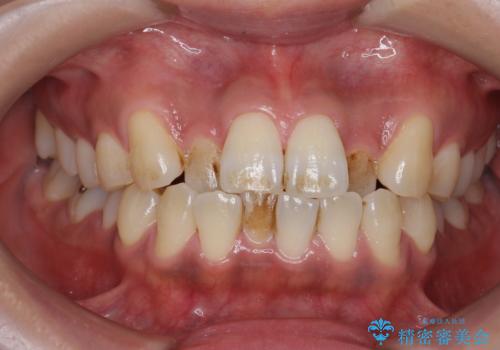

全体的な治療の開始前に着色取り